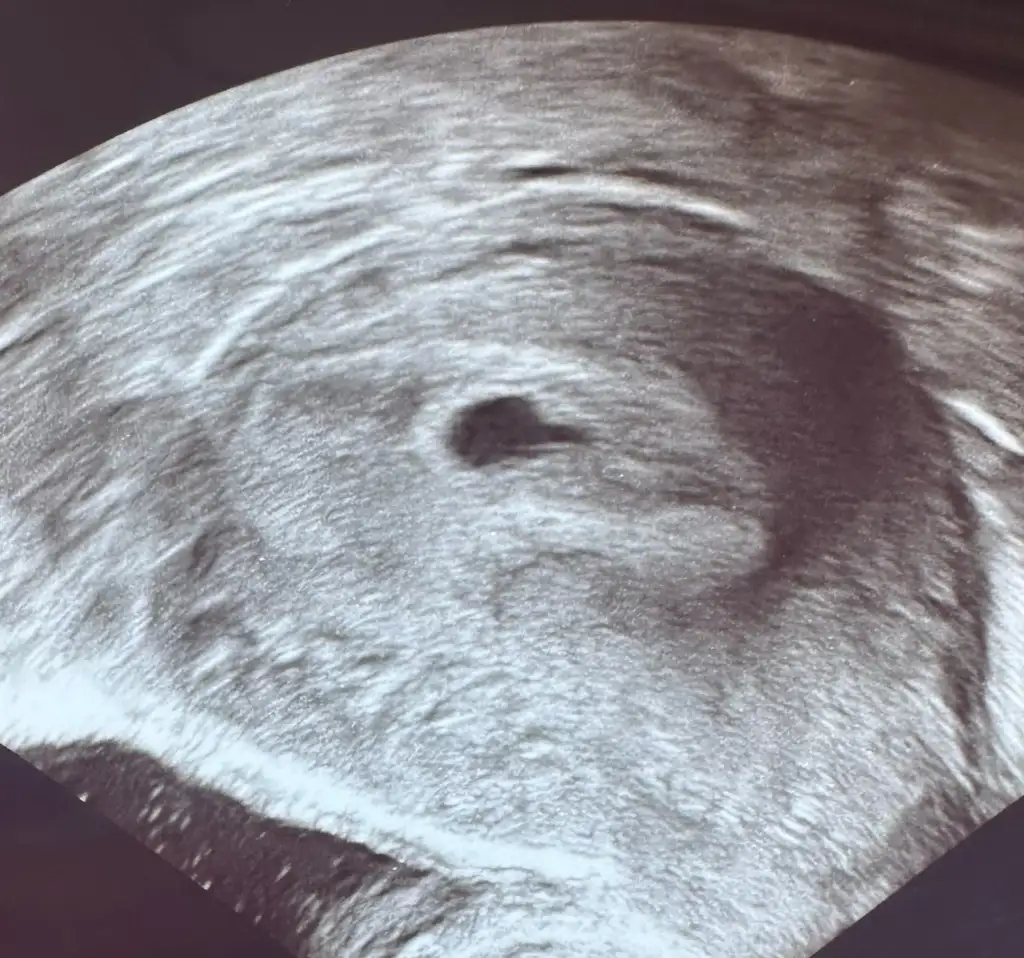

Kaset testler silik çıkarıyor beta iyice yükselene kadar. Erken gebelik testleri daha hassas olduğu için daha koyu çıkarKızlar ben bugün tekrar test yaptım birincisi ilk yaptığımda ikincisi biraz daha kuruduğunda ama hala emin olamıyorum ya cumartesi yaptığımda bundan biraz daha silikti sanki ama regli de 5 gün geçti daha koyu olması gerekmiyo muydu